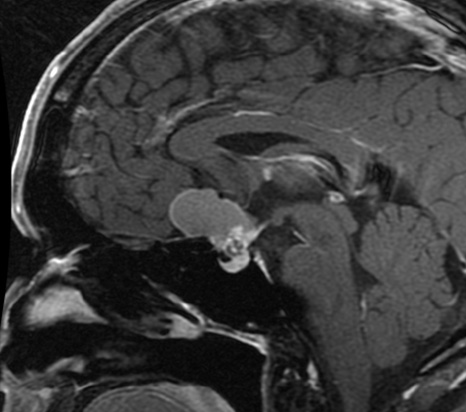

【髄膜腫】

鞍結節部髄膜腫とよばれ、髄膜腫の5~10%を占めます。

この部分の髄膜腫の特徴は、視神経の通り道への腫瘍浸潤が高率に認められることです。

そのため、小型(2.5cm未満)のものでも高頻度に視機能障害が生じることが知られています。

症状が出現する前に発見できた場合は、その時点で手術加療が推奨される特殊な髄膜腫です。